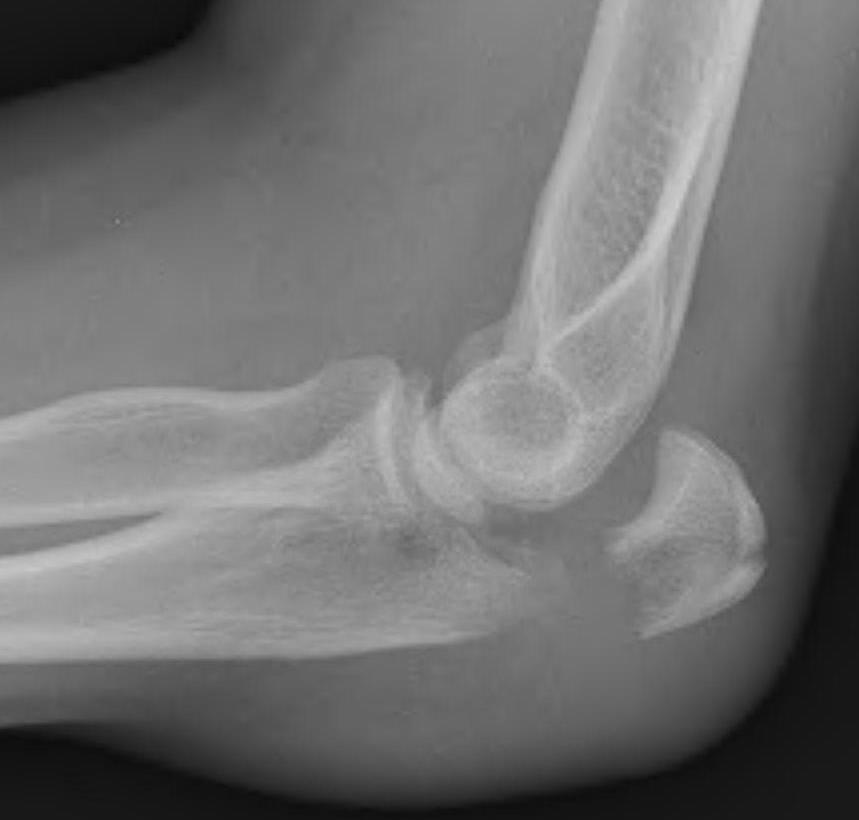

Anatomy

Proximal articular portion of the ulna

- greater sigmoid notch articulates with trochlea

- has a central bare area

- flexion / extension

Triceps insertion

- attaches to olecranon

- displaces olecranon fragment superiorly